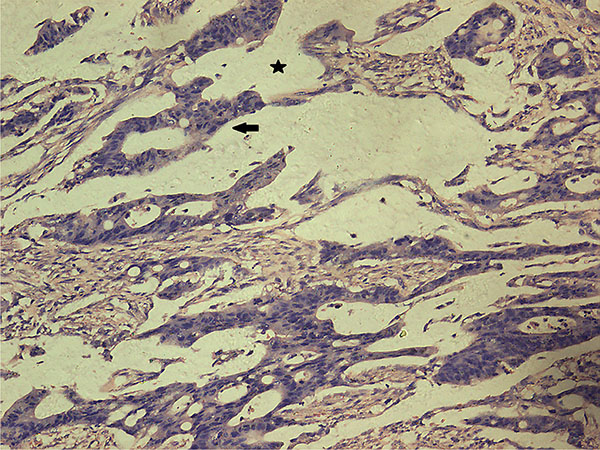

Histopathologic assessment of the primary tumor

Univariate analysis showed no differences in the tumor regression grade, incidence of T downstaging, neural invasion, or mesenteric tumor nodules (P > 0.05) between the ypN+ and ypN‒ groups. The ypN+ patients had significantly less differentiated tumors (P = 0.001), higher ypT stage (P = 0.013), and a higher incidence of lymphovascular invasion (9.8% vs. 1.2%, P = 0.038) than ypN‒ patients (Figures 2–3). In addition, mucinous or signet ring cell adenocarcinomas (poorly differentiated histological subtypes) were more commonly observed in ypN+ patients than in ypN- patients (P < 0.001) (Table 2, Figures 4–5).

Figure 4: Characteristic histological features of mucinous adenocarcinoma (H.E. staining, 200× magnification). Extracellular mucinous lakes (star) and clusters of mucinous cancer cells (arrow).